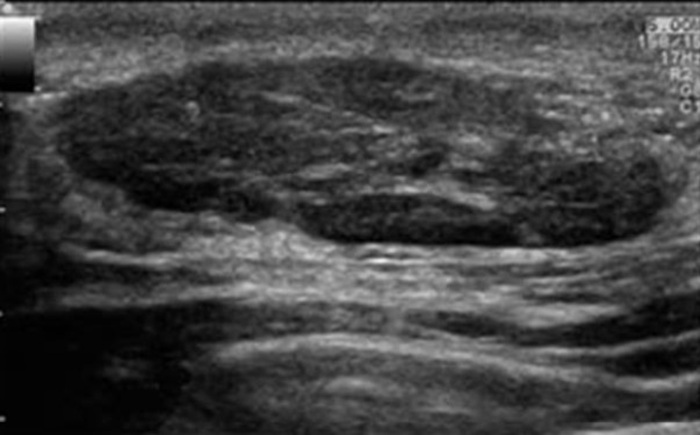

Что показывает сканирование

Ультразвук дает детальные изображения мышц, сухожилий, суставов. Обычно оценивают:

- Выявление опухолей, кист. Диагностика может обнаруживать новообразования, кисты, которые могут потребовать дополнительного лечения.